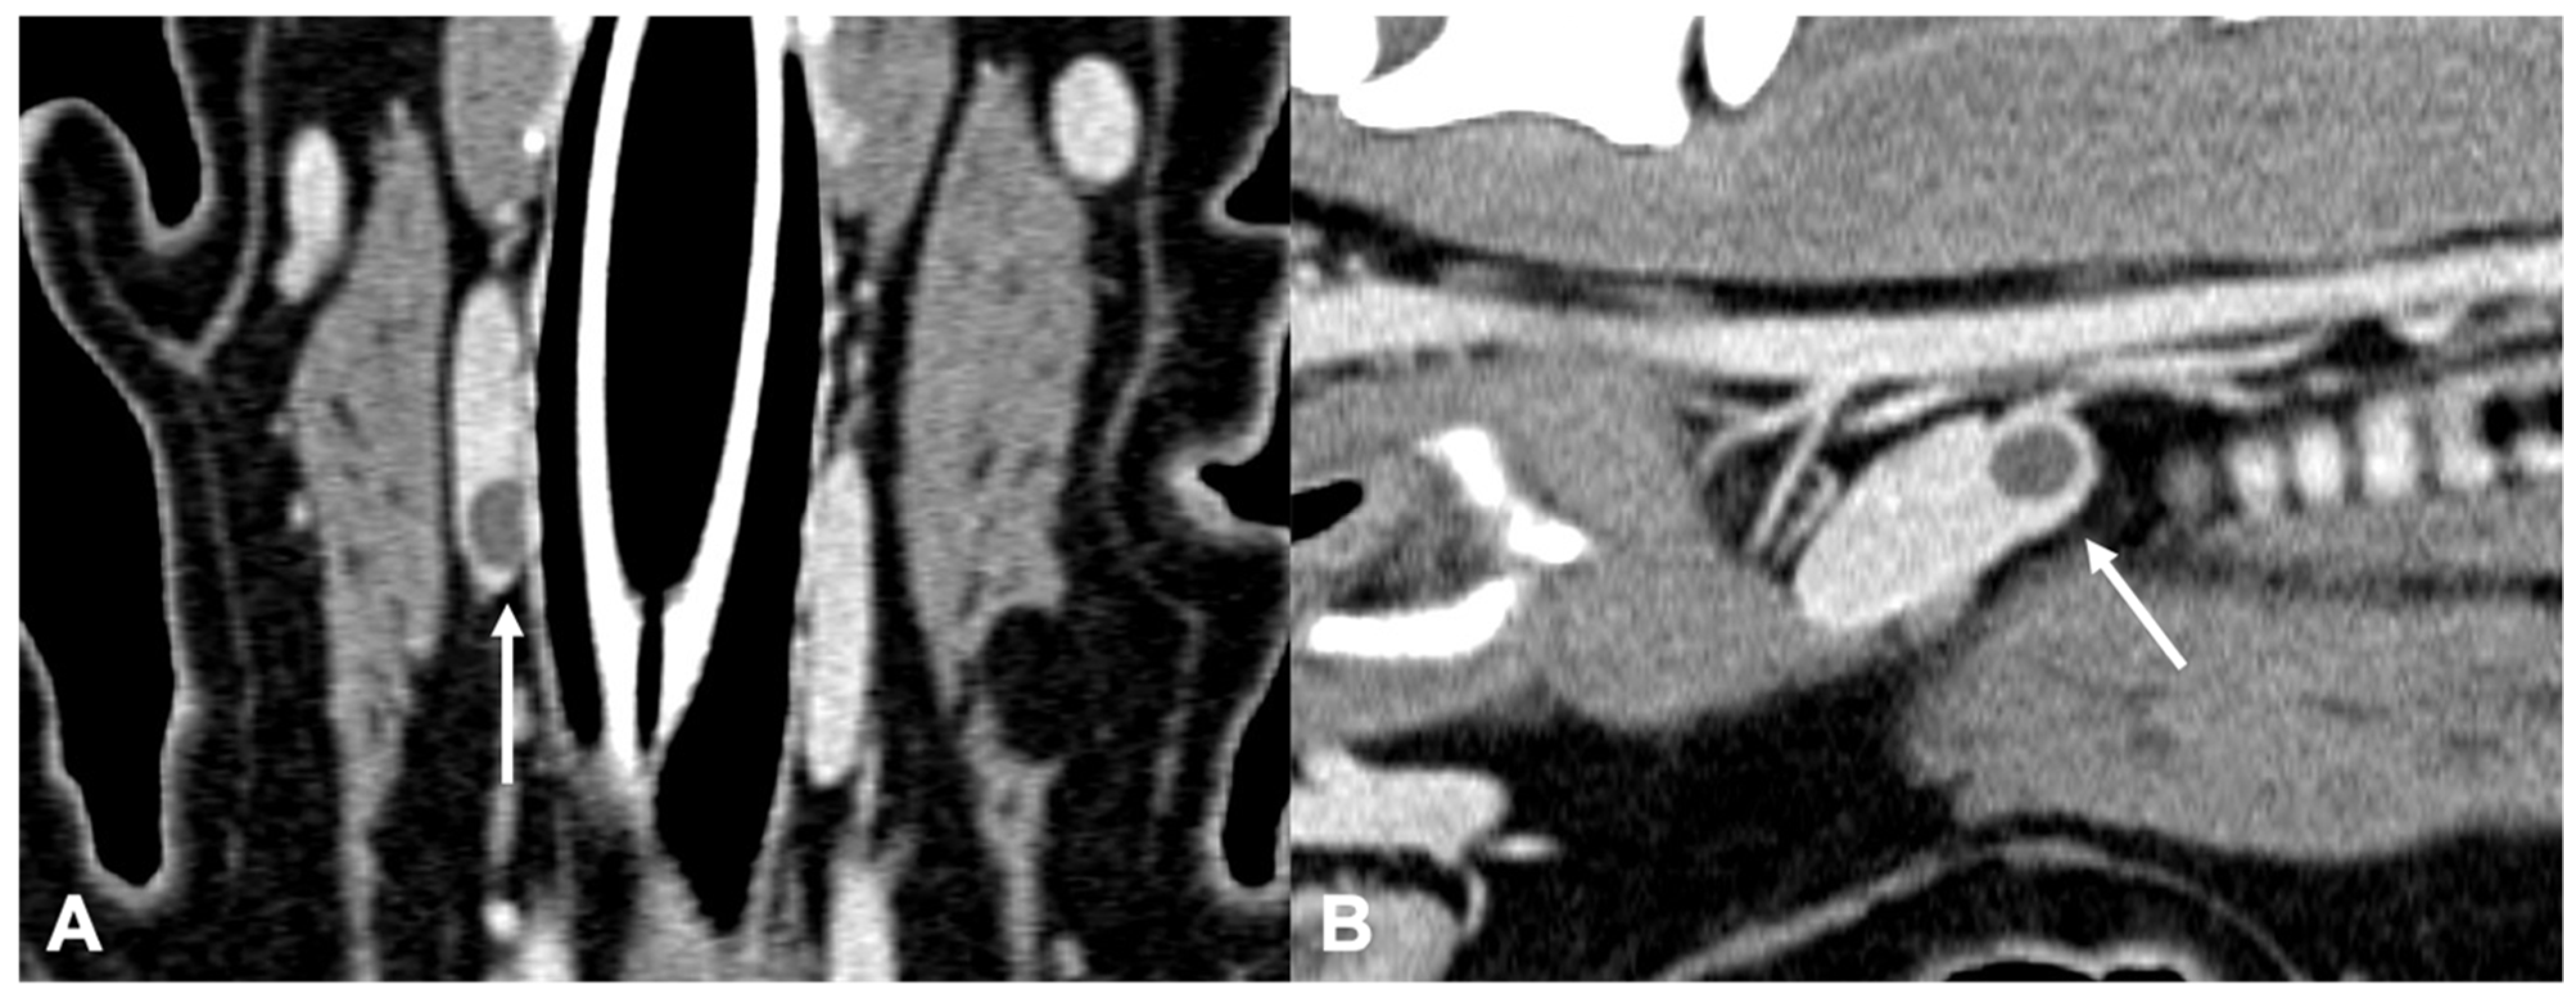

a and 2bA dog with primary hyperparathyroidism. Note the bone loss on... Download Scientific What Is Hyperparathyroidism In Dogs Hyperparathyroidism is a medical condition related to the parathyroid glands, in which over active parathyroid glands cause abnormally high levels of. What is canine primary hyperparathyroidism? In dogs, hypercalcemia is often associated with tumors (especially lymphoma, anal sac tumors, and multiple myeloma), an underactive adrenal. Primary hyperparathyroidism (phpt) is a rarely. Hyperparathyroidism in dogs is a condition that happens when. What Is Hyperparathyroidism In Dogs.